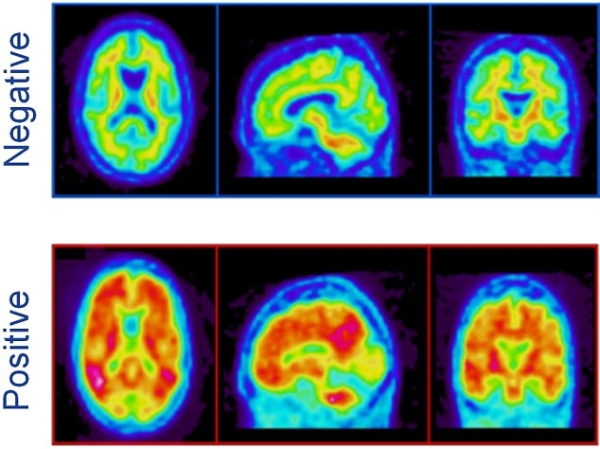

Unii oameni au avut semne fizice ale bolii. După ce s-a observat acest lucru, le-a fost scanat creierul, iar rezultatul scanării nu a relevat niciun simptom. Aceşti oameni sunt, în general, consideraţi ca fiind „extrem de inteligenţi”. De cele mai multe ori, ei au funcţii „înalte de conducere cu putere decizională” şi au „o mulţime de bani în bancă”, susţin oamenii de ştiinţă.